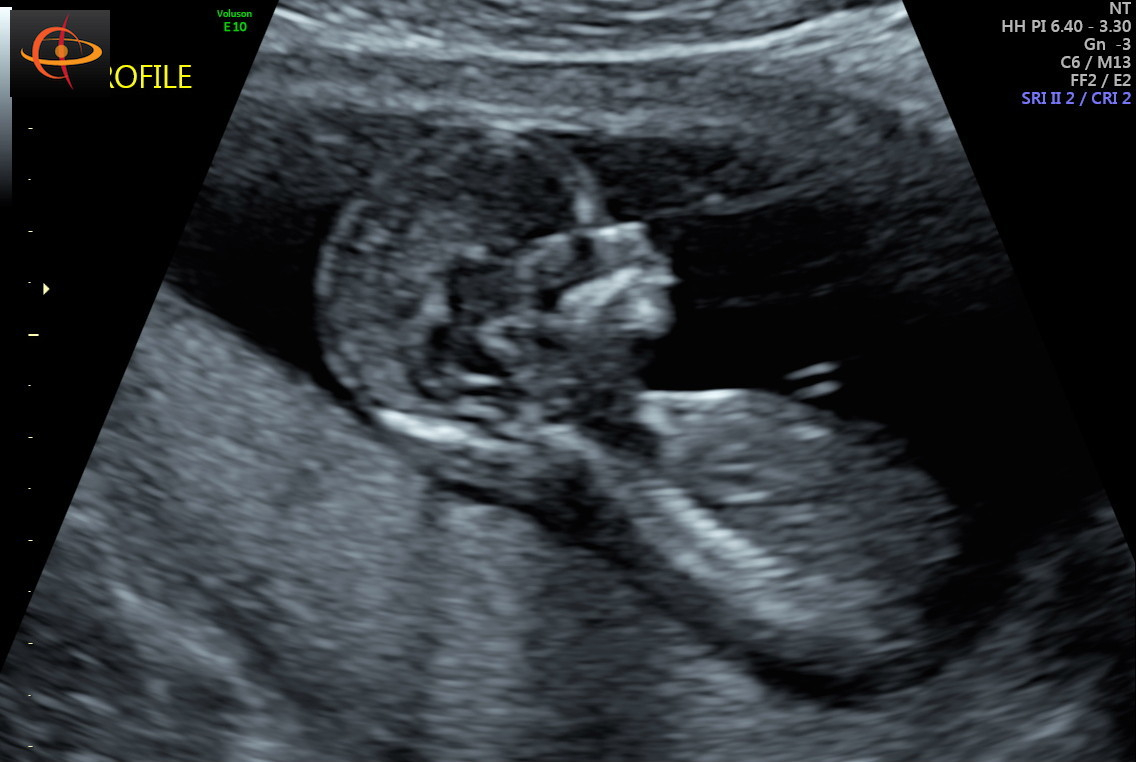

Shots from our NT scan at 12 weeks + 3 days. Measuring right on track, and the tech thought Baby B looked like a boy!